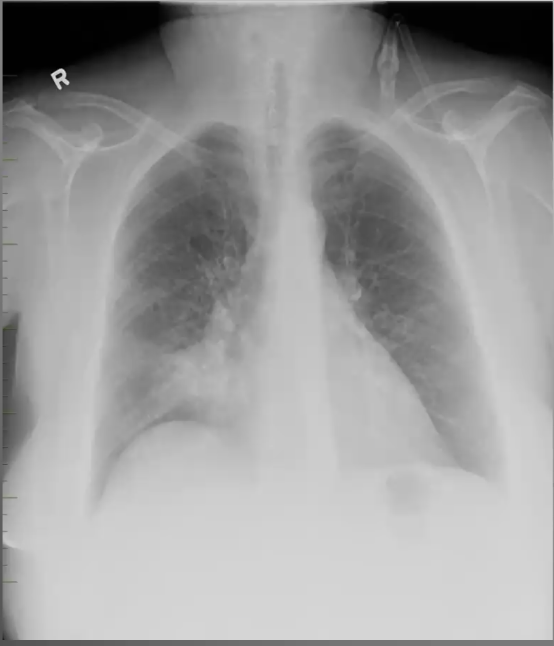

What’s your diagnosis?

Right lower lobe pneumonia because you have a right heart border (no silouhette sign) and a spine sign